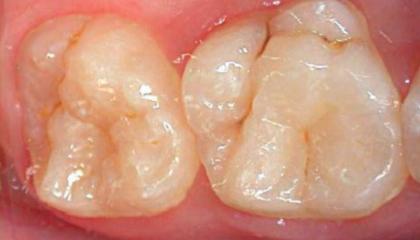

• Fissure sealants2

Fissure sealants AFTER